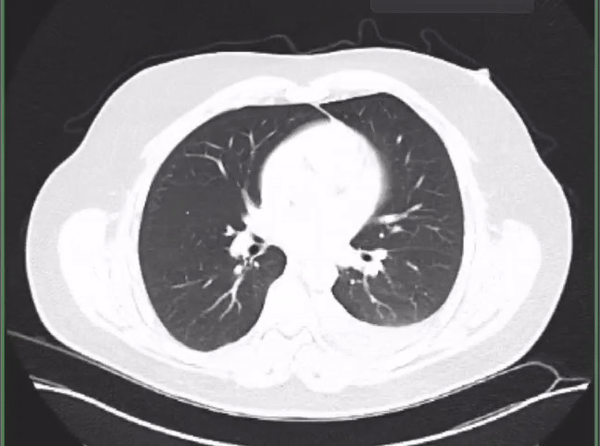

I got to the hospital emergency department and got seen. We spent about 6 hours there as they checked me and did chest x-rays and a CT scan. The hard part for me was laying down or taking in deep breaths. It was hard to breath, it just hurt when my chest expanded to a certain point.

After the tests, they didn’t find anything. The doctor did say my blood work hinted at a clot, but they didn’t see one. I also had a little fluid in a lung. Since they didn’t find anything, they suggested it may be muscle or skeletal related. The doctor prescribed me pain medication and a muscle relaxer.

The process was similar. I got brought in, and they did another chest x-ray and CT scan. This time, they saw a clot in each of my lungs. The ER doctor thanked me for listening to my body and coming in. They soon started me on heparin as I waited in the emergency department for a room to open up. I’m being admitted for observation and to do more testing.